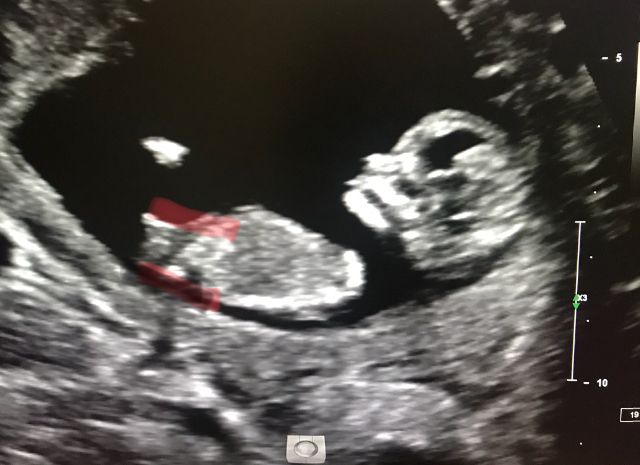

Boy or girl !?!? 12.3 weeks

Girlguess

I’m guessing girl too

I'm torn on this and think it could go either way (I'm not an expert at all) Have you got amy more pics?